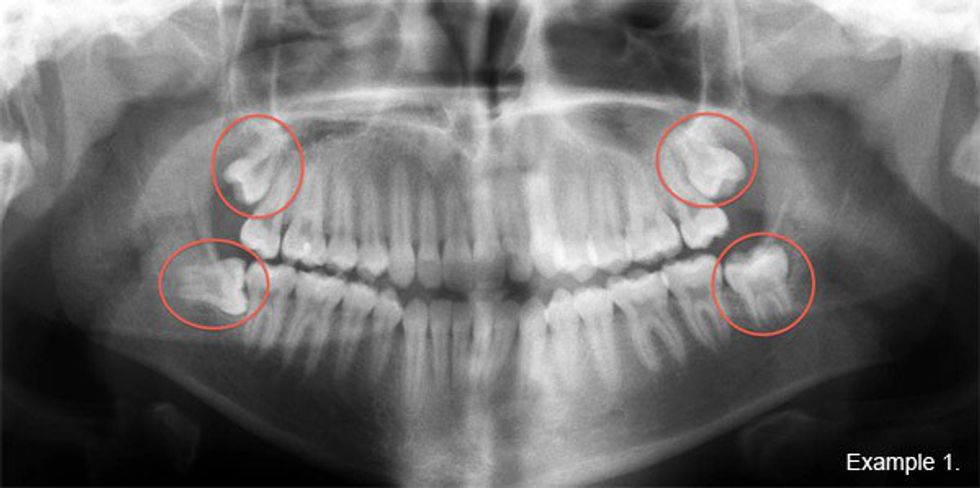

5.) The consultation: how many? What's going to happen?